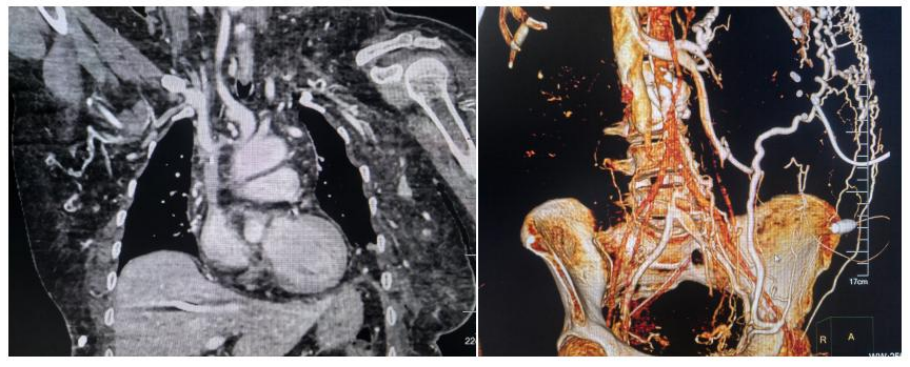

8月26日,中南大学湘雅三医院放射介入病房成功为一例双侧无名静脉及髂静脉闭塞的尿毒症患者再建“生命线”,迅速解决了患者无法透析的问题,为其再创生活希望。患者术后恢复良好,术后第二天康复出院。本次经皮肝静脉长期透析管置入为湖南省首例,国内亦鲜有报道,体现了医院血透通路MDT团队处理疑难、复杂血透通路疾病的能力水平。

该患者因右侧颈内静脉-双侧无名静脉-上腔静脉以及双侧股-髂静脉闭塞失去了经深静脉长期透析管置管机会,只能另寻其他路径。放射介入病房梁琪副教授在详细评估患者病情后,考虑可尝试经皮穿刺肝静脉后经肝静脉-下腔静脉-右心房透析管置入,但上述方案非常规手术操作,文献也鲜有记载。与患者及家属反复沟通后,患者家属表示没有透析通路患者也无法存活,即使冒再大的风险也要尝试。当天晚上,血透通路MDT团队展开多学科讨论,精心设计手术方案与风险预案,先由彩超科刘稳刚副教授行彩超引导下经皮穿刺肝静脉,成功置入导丝,然后由放射介入病房梁琪团队联合肾内科血透室徐勇博士在DSA引导下行经肝静脉-下腔静脉-右心房透析管置入术,手术共历时40min,术中患者生命体征平稳,无任何并发症发生,术后第二天,患者试用透析通路功能良好,顺利出院。